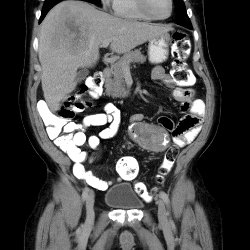

CT